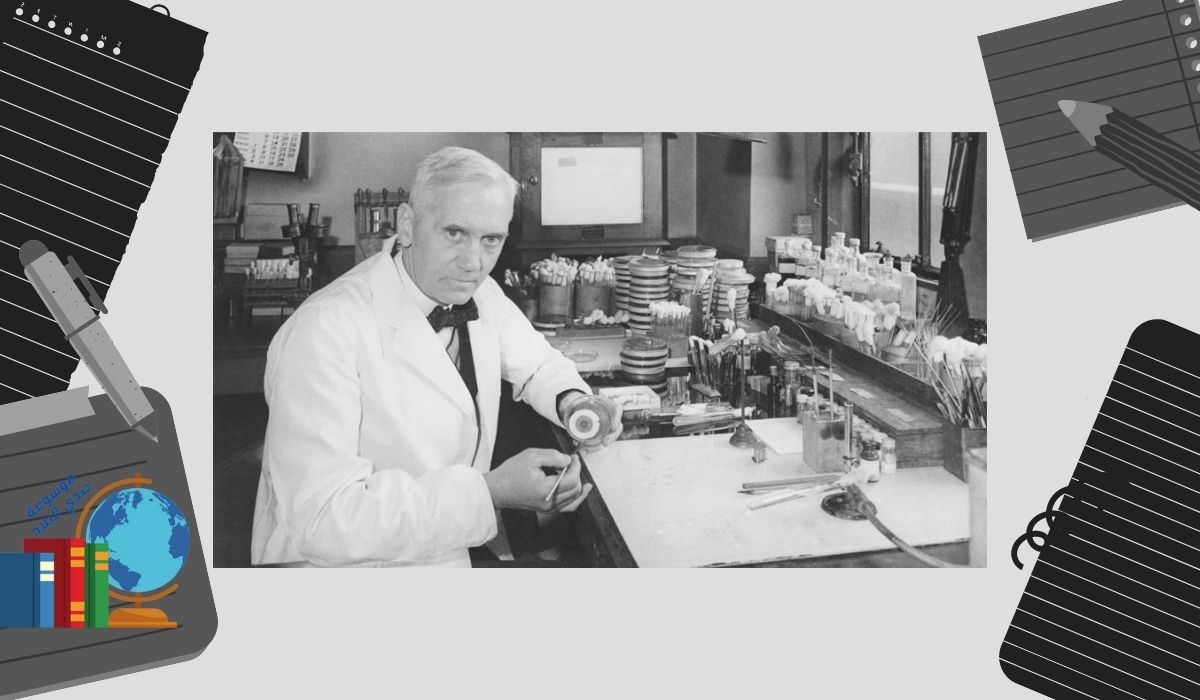

إنها واحدة من أشهر قصص الاكتشاف في التاريخ. في عام 1928، لاحظ العالم الاسكتلندي ألكسندر فليمنج وجود طبق بتري مملوء بالبكتيريا في مختبره وغطاءه مفتوح جزئيًا عن طريق الخطأ. أصبحت العينة ملوثة بالعفن، وفي كل مكان كان العفن، ماتت البكتيريا. وتبين أن هذا العفن المضاد الحيوي هو فطر البنسليوم، وعلى مدى العقدين التاليين، قام الكيميائيون بتنقيته وتطوير عقار البنسلين ، الذي يحارب عددًا كبيرًا من الالتهابات البكتيرية لدى البشر دون الإضرار بالبشر أنفسهم.

تم إنتاج البنسلين والإعلان عنه بكميات كبيرة بحلول عام 1944. ينصح هذا الملصق المرفق بصندوق بريد على جانب الرصيف جنود الحرب العالمية الثانية بتناول الدواء لتخليص أنفسهم من الأمراض التناسلية.

يعاني حوالي 1 من كل 10 أشخاص من رد فعل تحسسي تجاه المضاد الحيوي ، وفقًا لدراسة نشرت عام 2003 في مجلة Clinical Reviews in Allergy and Immunology. ومع ذلك، قال الباحثون إن معظم هؤلاء الأشخاص أصبحوا قادرين على تحمل الدواء.